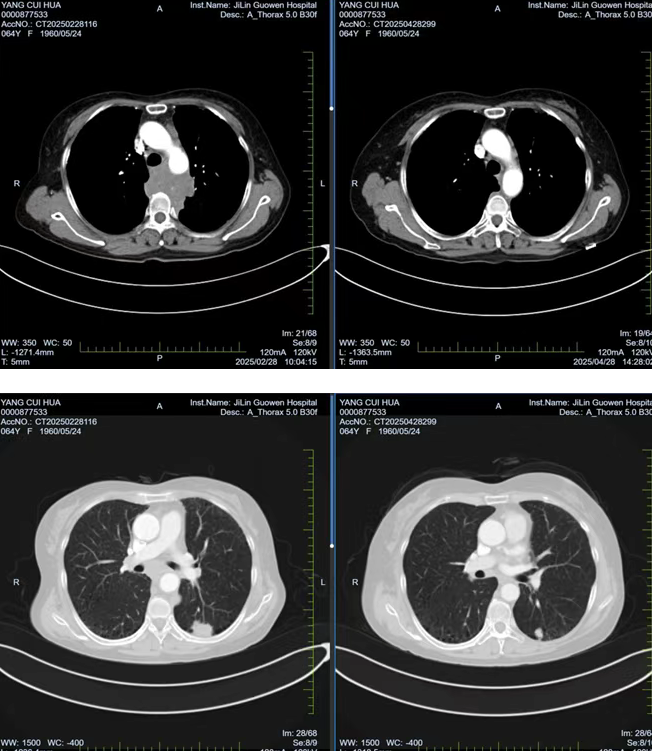

張阿姨因胸背部疼痛持續(xù) 1個月且逐漸加重,在當(dāng)?shù)蒯t(yī)院檢查時發(fā)現(xiàn)左肺存在腫物,初步考慮為惡性腫瘤。經(jīng)熟人介紹,了解到我院在腫瘤??萍膊≈委煼矫娴膬?yōu)勢后,該患者前往我院就診。胸部腫瘤放化療二科為其安排了 PET/CT 檢查,并對左側(cè)鎖骨上腫大淋巴結(jié)進行穿刺活檢,最終明確診斷為左肺下葉高級別神經(jīng)內(nèi)分泌癌,臨床分期為 cT1cN3M0 IIIb 期,且縱隔轉(zhuǎn)移淋巴結(jié)已侵犯椎體,患者因劇烈疼痛,生活質(zhì)量受到嚴重影響。

經(jīng)過 1 周期的免疫聯(lián)合化療后,患者的胸背部疼痛逐漸減輕,目前患者疼痛癥狀已得到改善,生活質(zhì)量得到了顯著提升。